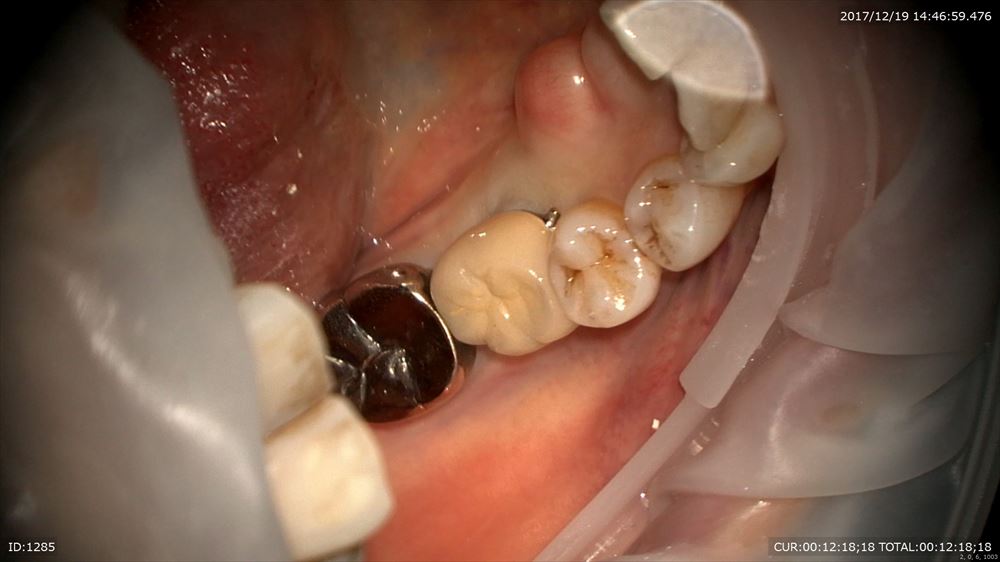

さて今日はマイクロスコープ治療での歯周病治療

若年性歯周炎

A.a菌による感染症が細菌検査で判明。こんなに歯石が。(16倍)

もう1つのケースはインプラントと再生療法を同時に行った方の被せ物セットもマイクロスコープ治療で

歯周病だったと思えないくらい歯肉は綺麗。患者さまのプラークコントロールに助けられています。

セット。お正月が楽しみ!お餅。数の子!!